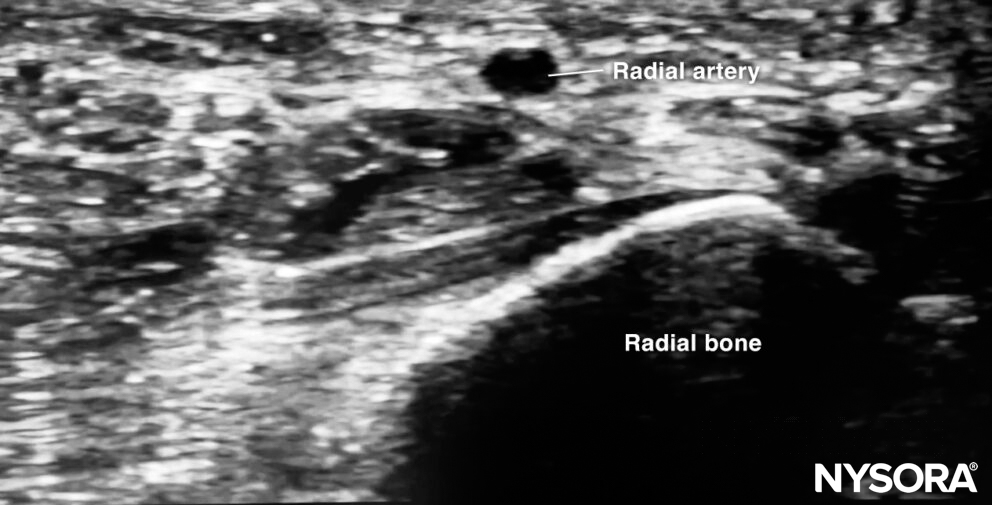

Sonoanatomy for radial artery cannulation.